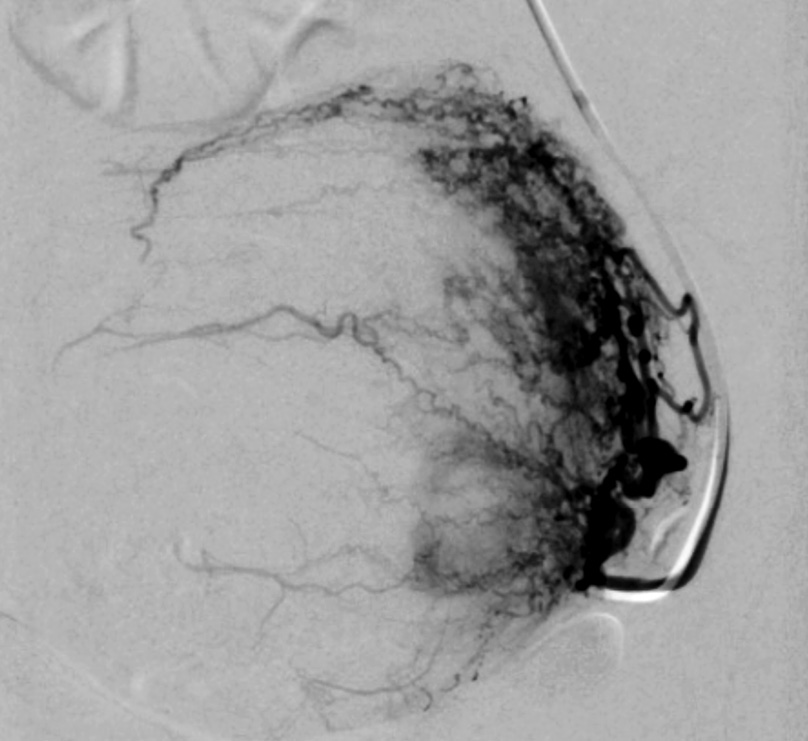

Выполнены пункция и катетеризация правой лучевой артерии в ретроградном направлении. Далее катетером выполнена селективная катетеризация правой и левой маточных артерий. Выявлена миома матки больших размеров с выраженным перифиброидным сплетением. При проведении ангиографии брюшной аорты и таза дополнительных источников кровоснабжения не выявлено. Катетер по проводнику проведен последовательно в горизонтальные сегменты левой и правой маточных артерий, питающих узлы (рис. 8, 9). Проведена эмболизация насыщенными гадотеридолом микросферами до стаза контраста в дистальных сегментах маточных артерий. Рентгеновский контроль эффективности эмболизации – рис. 10, 11. Катетер и интродьюсер удалены. Наложена давящая асептическая повязка.

Рис. 8. Клинический пример №2. Ангиограмма правой маточной артерии до ЭМА. / Fig. 8. Clinical case 2. Angiogram of the right uterine artery before UAE.

Рис. 9. Клинический пример №2. Ангиограмма левой маточной артерии до ЭМА. / Fig. 9. Clinical case 2. Angiogram of the left uterine artery before UAE.

Рис. 10. Клинический пример №2. Ангиограмма правой маточной артерии после ЭМА. / Fig. 10. Clinical case 2. Angiogram of the right uterine artery after UAE.

Рис. 11. Клинический пример №2. Ангиограмма левой маточной артерии после ЭМА. / Fig. 11. Clinical case 2. Angiogram of the left uterine artery after UAE.